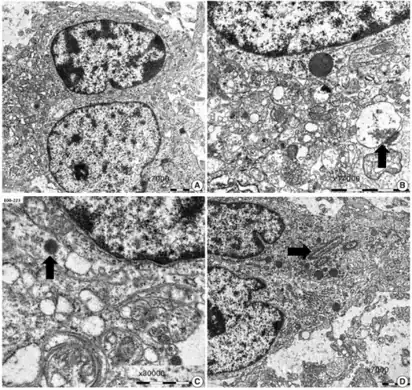

a-d)Ultrastructural findings of dysembryoplastic neuroepithelial tumors -

A dysembryoplastic neuroepithelial tumour is commonly diagnosed in patients who are experiencing seizures with magnetic resonance imaging (MRI), electroencephalogram (EEG).[4] A DNT is most commonly diagnosed in children who are experiencing seizures, and when given medication do not respond to them. When an MRI is taken there are lesions located in the temporal parietal region of the brain.[4]